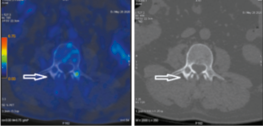

На совмещенных ПЭТ/КТ- и КТ-проекциях с использованием 18-фтордезоксиглюкозы в правом надпочечнике определяется объемное образование размером 79×54×41 мм с ровным нечетким контуром, неоднородной структуры за счет наличия гиподенсных аметаболических участков некроза с повышенной метаболической активностью фтордезоксиглюкозы SUVmax 7.25. Верхнелатеральным контуром образование прилежит к нижней поверхности печени (граница четко не дифференцируется), нижним контуром – к верхнему полюсу почки (жировая прослойка прослеживается), а медиально – к ножке диафрагмы (рис. 1, 2).

Рис. 2. Пациент У., 52 года. Аксиальная ПЭТ/КТ- (а) и КТ-проекция (б). В правом надпочечнике опухоль размером 79х54х41 мм (стрелка), SUVmax 7.25.

Fig. 2. A 52-year-old patient U. PET/CT (a) and CT images in axial projection (b). A 79×54×41 mm mass (arrow) in the right adrenal gland, SUVmax 7.25.

Рис. 4. Пациент У., 52 года. Аксиальная ПЭТ/КТ- (а) и КТ-проекция (б). В верхнесуставном отростке L3 очаг деструкции размером 10х15 мм (стрелка), SUVmax 3.83.

Fig. 4. A 52-year-old patient U. PET/CT (a) and CT images in axial projection (b). The lytic lesion (10×15 mm) (arrow) in right superior L3 articular process, SUVmax 3.83.

позвоночного канала с повышенной фиксацией радиофармпрепарата с метаболической активностью SUVmax 3.83 (рис. 4).